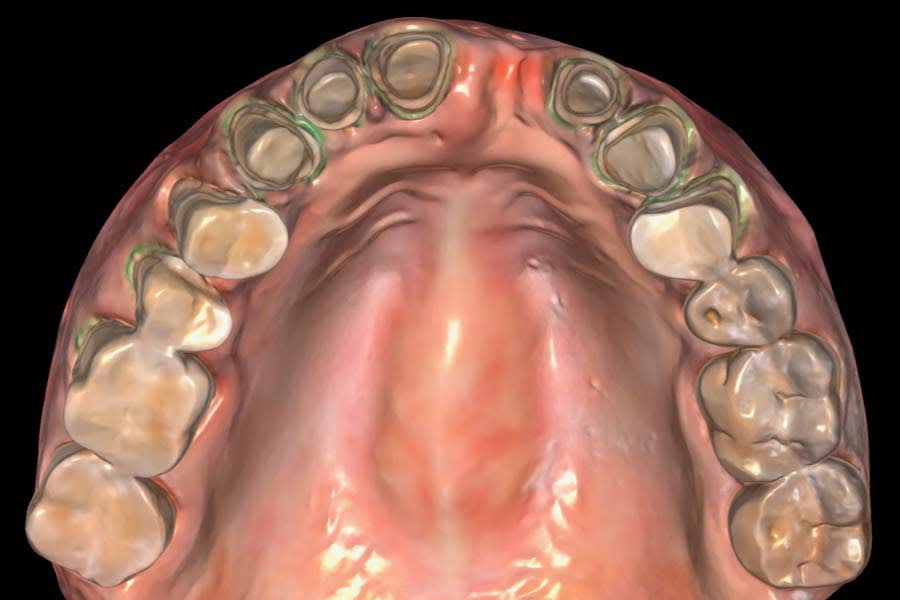

Digital smile design was generated using a biomimetic tooth library in a virtual treatment planning software (Smilecloud 3DNA, Smilecloud, smilecloud.com) and presented to the patient for discussion (Figure 5 and Figure 6). A proposed soft-tissue design that included root coverage procedures and an implant placement option for the replacement of tooth No. 30 was also reviewed. Surgical procedures would be deferred because the patient was planning a relocation within 2 months; however, she expressed interest in pursuing these procedures in the future. Based on the patient’s chief complaint, esthetic goals, and timeline, the treatment plan included replacing the existing FDP and restoring the worn dentition with a combination of CAD/CAM lithium-disilicate partial-coverage indirect restorations and direct composite restorations at a 2 mm increased OVD.

The patient-approved smile design was used as a guide to complete a functional wax-up using a virtual semi-adjustable articulator (Stratos® 300, Ivoclar, ivoclar.com) at 2 mm increased OVD. The printed model was used to fabricate a silicone matrix for chairside provisionalization. The existing anterior FDP was sectioned and removed, and preparations were refined to ideal contours. Immediate dentin sealing was performed, and the teeth were provisionalized with bisacryl material. Full-mouth preparation was completed, maintaining the established vertical dimension with the bonded mock-up on unprepared teeth and provisional restorations on prepared teeth.